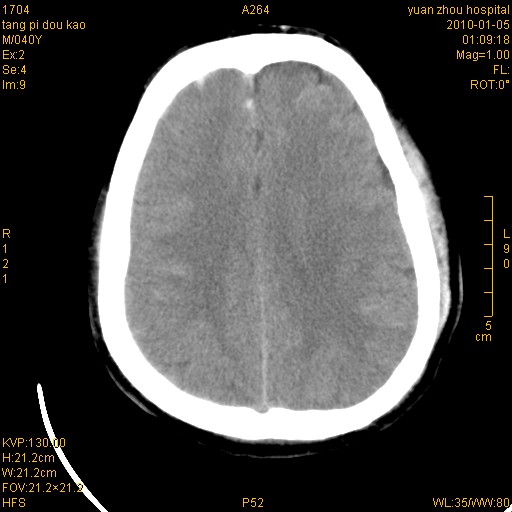

标题: CT23986:M 40Y 外伤数小时 [打印本页]

标题: CT23986:M 40Y 外伤数小时

双侧额叶 右侧大脑脚区多发血肿伴蛛网膜下腔出血!

1)左侧颞枕部硬膜外血肿。2)右侧额部硬膜下血肿。3)双侧额叶及右侧基底节下部脑挫裂伤。4)蛛网膜下腔出血。5)脑水肿。6)左侧前组筛窦及左侧额窦炎症。

前纵裂池的出血是硬膜下还是蛛网膜下腔?右额叶深区血肿还是基底节血肿?

病人很清醒。